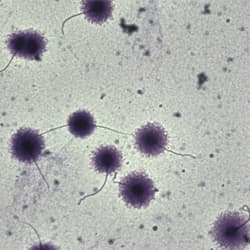

Motility

Tracks, velocities, classification

Counts and % counts: total count, motile, progressive motile, rapid/medium/slow/static classification. Mean velocities: VAP, VCL, VSL, and related metrics (per manufacturer listing). Track overlay for movement visualization. Dose calculation. Read from image sequences in different formats (bmp, tiff, jpeg, etc.). Generate comprehensive statistics for one or several fields; transfer results to Microsoft Excel; custom report generator with results and images; slow-motion playback of stored sequences for behavioral studies.